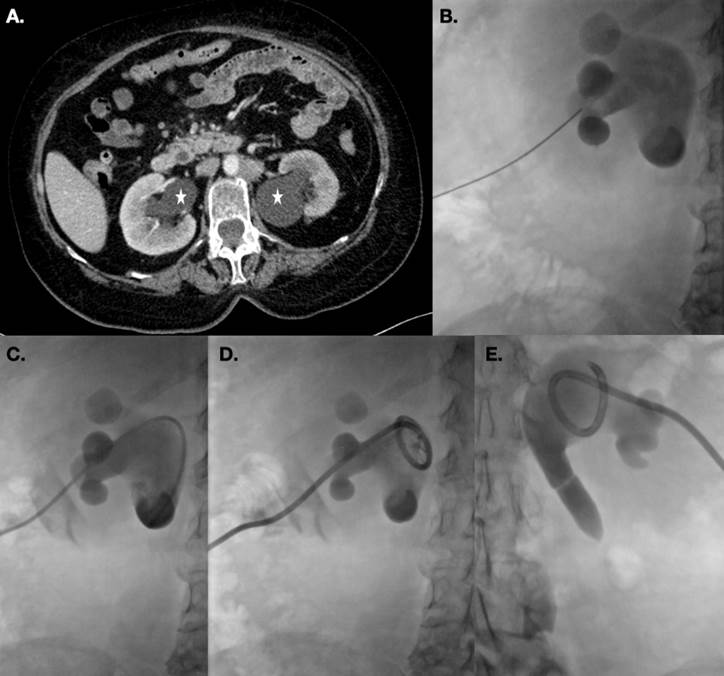

Uno de los escenarios más comunes para realizar derivación de la vía urinaria es la hidronefrosis, que se define como la dilatación del sistema urinario del riñón (cálices, infundíbulos y pelvis). Se debe establecer la causa de esta, ya que en muchas ocasiones se trata de una etiología que puede tratarse y evita la progresión a daño renal. Las causas más comunes de hidronefrosis son urolitiasis, obstrucción secundaria de las uniones ureterovesicales y obstrucción maligna secundaria en diferentes niveles de la vía urinaria. En este contexto, el radiólogo intervencionista suele ser interconsultado para derivación de la vía urinaria mediante nefrostomías, y, dependiendo de la causa, será unilateral o bilateral.2,4 (Figura 5).

(A) Paciente femenino con antecedente de cáncer cervicouterino e hidronefrosis bilateral. (B y C) se realiza nefrostomía mediante guía sonográfica y fluoroscópica. (D) se coloca catéter de nefrostomía y se repite el procedimiento en riñón contralateral (E).

Figura 5

En algunas ocasiones, sobre todo hablando de hidronefrosis secundaria a obstrucción que involucra la unión ureterovesical, el ascenso de catéter doble J de forma retrógrada puede ser difícil de conseguir. Por tal motivo, una de las causas más frecuentes en las que se interconsulta al radiólogo intervencionista es en estos casos y es para colocación de nefrostomías. Sin embargo, se puede realizar la colocación de catéteres doble J de forma anterógrada. La punción se realiza con la misma técnica empleada para nefrostomía, con la excepción de avanzar guía para flanquear el sitio de estenosis y conseguir el paso de la guía a la vejiga. Una vez conseguido el paso de la guía, dependiendo del grado de estenosis, puede intentarse colocar el catéter doble J o realizar plastía con catéter-balón del sitio de obstrucción previo a la colocación del catéter doble J (Figura 6). De forma excepcional se puede colocar un estent urinario en el sitio de estenosis.2 Una vez colocado el catéter doble J, la nefrostomía permanece como protección para el sitio de acceso, y se deja a derivación durante 48 horas, después se continúa cerrado durante 48 a 72 horas más, para finalmente ser retirado. Antes de ser retirado, se debe confirmar que el catéter doble J es funcional mediante una urografía.7 (Figura 7).

Paciente con antecedente de cáncer cervicouterino y obstrucción al paso del medio de contraste en unión ureterovesical (flecha en A). Se avanza guía hidrofílica con catéter multipropósito hasta flanquear la obstrucción (B) y conseguir el avance del sistema al interior vesical (C). Se intercambia el catéter multipropósito por catéter balón y se realiza plastía del sitio de estenosis (flecha en D).

Figura 6 Paciente con antecedente de cáncer cervicouterino y obstrucción al paso del medio de contraste en unión ureterovesical

(A) Paciente masculino portador de nefrostomías por antecedente de hidronefrosis secundaria a invasión vesical de cáncer de próstata. Durante el primer recambio de catéter muestra paso del medio de contraste a vejiga. (B) Se avanza guía 0.035” a vejiga y se intercambia por catéter doble J (C). Posteriormente se dejan nefrostomías a derivación durante 48 horas y después cerradas durante 72 horas más. (D) Se realiza urografía en la que se observa adecuado paso del medio de contraste desde nefrostomías a vejiga, a través de catéteres doble J. (E) Se decide retiro de nefrostomías.

Figura 7